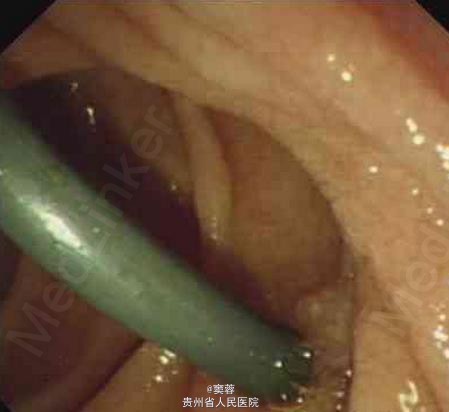

患者男性,60岁,有慢性胆囊炎及胆囊结石病史20年。患者于2006年6月中旬无诱因出现尿黄、皮肤黄,无腹痛、发热等,在当地医院接受经内镜逆行胰胆管造影(ERCP)及胆管塑料支架置入引流。ERCP造影提示患者有肝门部占位。